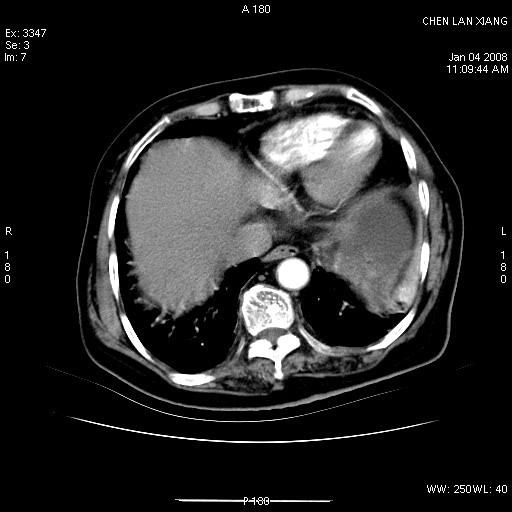

女,76岁,腹痛3-4天,b超示:肝内实性肿物,胆囊强回声,胆总管扩张.

考虑:1、胆总管下端结石伴梗阻性肝内外胆管扩张(肝左叶外侧段肝内胆管多发结石、胆管炎);

2、肿囊癌累及肝,不除外 黄色肉芽肿性胆囊炎。

1 胆总管末端结石伴肝内胆管结石,肝内外胆管扩张。2 胆囊扩大,胆囊壁不规则增厚,内见软组织密度影。考虑:慢性胆囊炎,不除外胆囊癌!

胆囊密度增高,增强后周边肝组织及胆囊窝下部周边软组织延时性不规则强化.然胆囊壁未见明显不规则增厚及肿块.左侧肝内胆管及胆总管下段结石伴胆系扩张.

考虑;胆囊炎(黄色肉芽肿性胆囊炎?),左侧肝内胆管及胆总管下段结石.

ct所见:1、 肝内胆管结石,肝内外胆管扩张。低位胆道梗阻,胆总管下端结石;2 胆囊扩大,胆囊壁不规则增厚

考虑:胆总管下端结石并肝内外胆管扩张,肝内胆管结石;

1)胆囊癌伴肝脏转移。2)胆总管下端结石、肝内胆管结石伴肝内外胆管扩张。